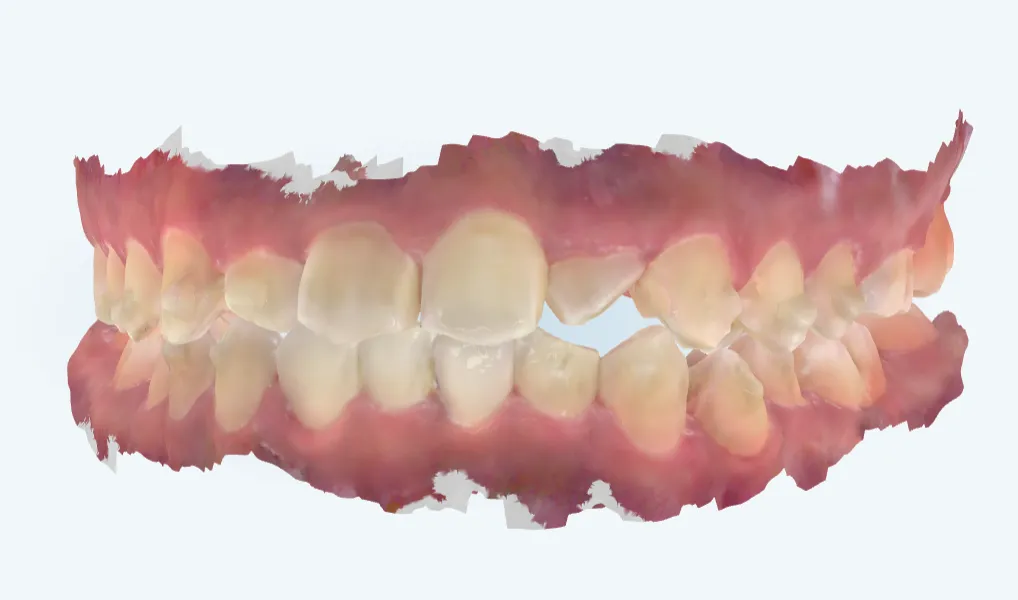

上にお示ししている画像もマウスピース矯正で上の2番目の歯がうまく動いてくれず、明らかに歯が短く見えて下の歯との間に隙間があることが分かります。

この患者様は他院様から引き受けた患者様で、マウスピース矯正で治療されていました。

当院でも引き続きマウスピース矯正でリカバリーできればと思っていましたがなかなか改善せず、ワイヤー矯正でリカバリーと提案させていただきました。